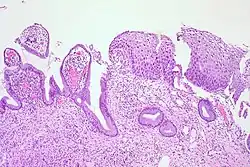

CIN 3 (Grade III)

• Severe dysplasia with undifferentiated neoplastic cells that span more than 2/3 of the epithelium

• May involve the full thickness

• May also be referred to as cervical carcinoma in situ

• CIN 3+ encompasses CIN 3, AIS, and cancer